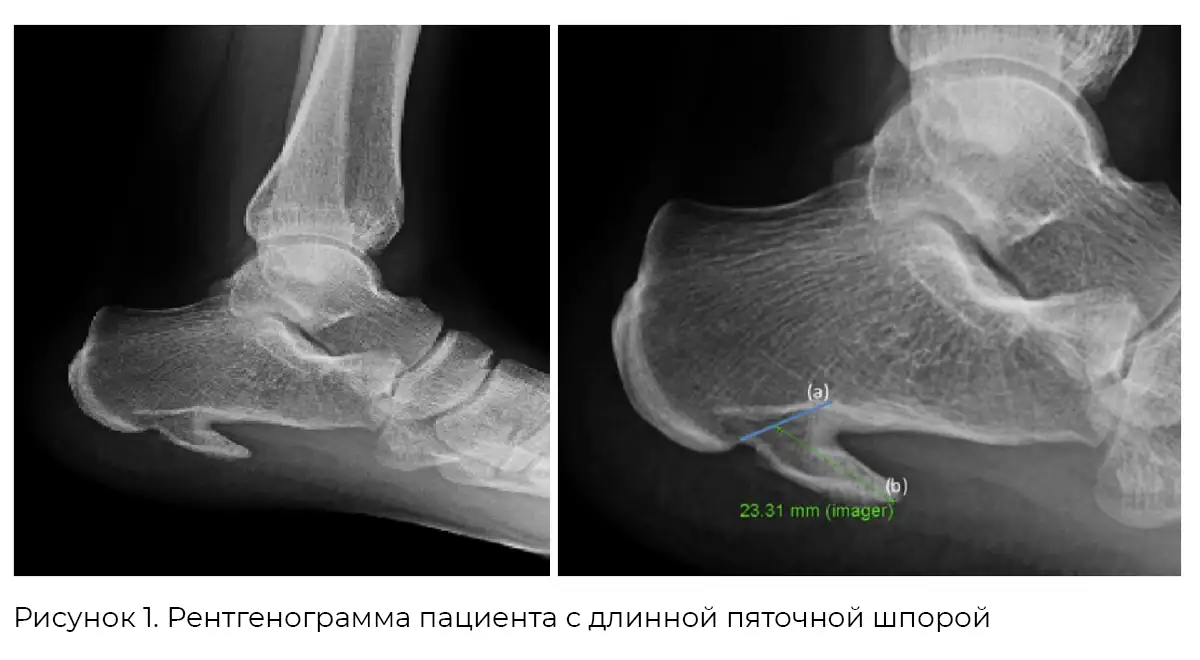

Однако бывают исключения. В литературе описан редкий случай: у молодого мужчины без сопутствующих заболеваний выявили длинную пяточную шпору, сопровождавшуюся болью и фасциитом [5] (рис. 1).